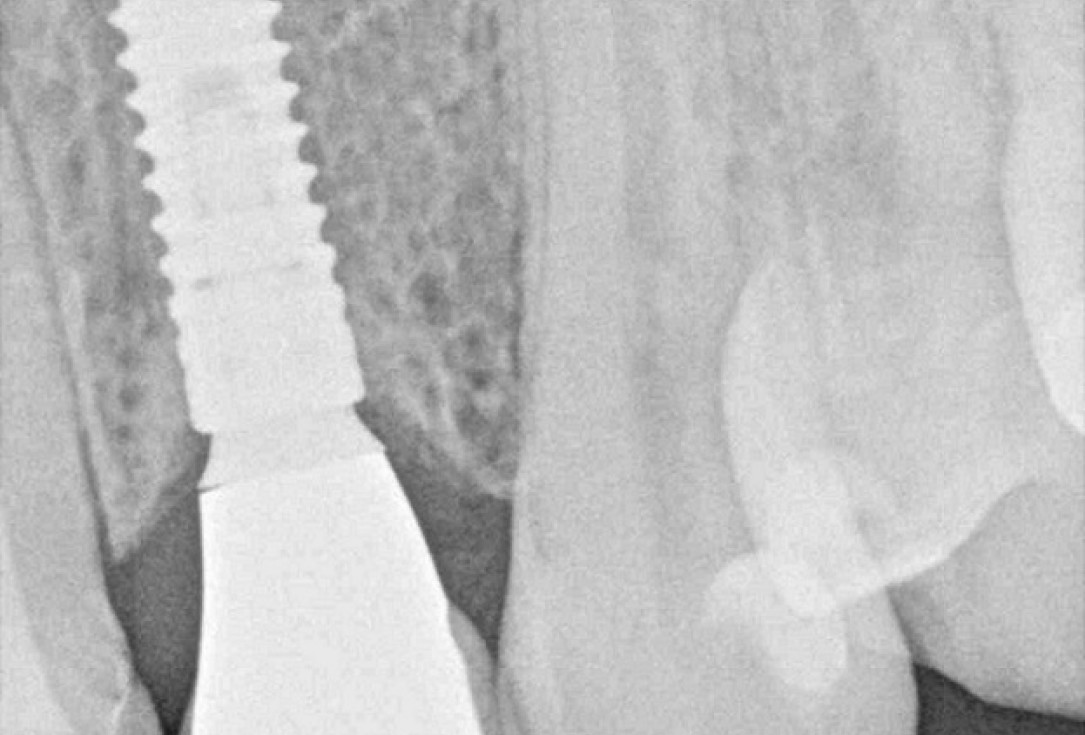

11/12 - X-ray control after 18 monthsSoft tissue thickening at immediate implant placement and GBR with mucoderm® and maxgraft® - Dr. A. Puisys